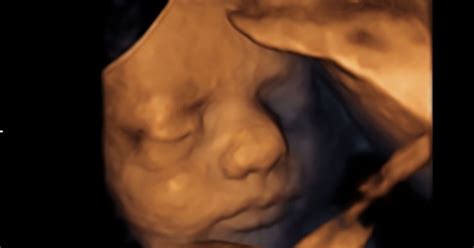

Otrok v 40. Tednu: Končno Velikost in Pripravljenost na Svet

V 40. tednu nosečnosti otrok doseže svojo končno porodno velikost. V povprečju je dolg približno 51 cm in tehta okoli 3100-3500 gramov. Če si ga predstavljate v naročju, je velik kot zelo velika buča. V zadnjih tednih si je nabral dovolj maščobnih zalog, ki zdaj predstavljajo približno 15 % njegove telesne teže. Ta maščobna plast mu bo pomagala pri termoregulaciji po rojstvu.

Otrokova jetra v tem času iz materinega krvnega obtoka absorbirajo več škroba, ki ga bo telo po rojstvu pretvorilo v glukozo, ključno obliko energije. Prvo mleko, kolostrum, ki ga bo otrok prejel po rojstvu, je bogato s pomembnimi protitelesi, ki krepijo njegov imunski sistem. Kosti lobanje še niso popolnoma zraščene, kar omogoča, da se med porodom nekoliko stisnejo, s čimer se olajša prehod skozi porodni kanal. Te vrzeli med kostmi se zaprejo šele približno 18 mesecev po rojstvu. V maternici otrok nima več veliko prostora, zato se zvije v značilen fetalni položaj z glavo navzdol v medenici, kjer čaka na svoj čas.